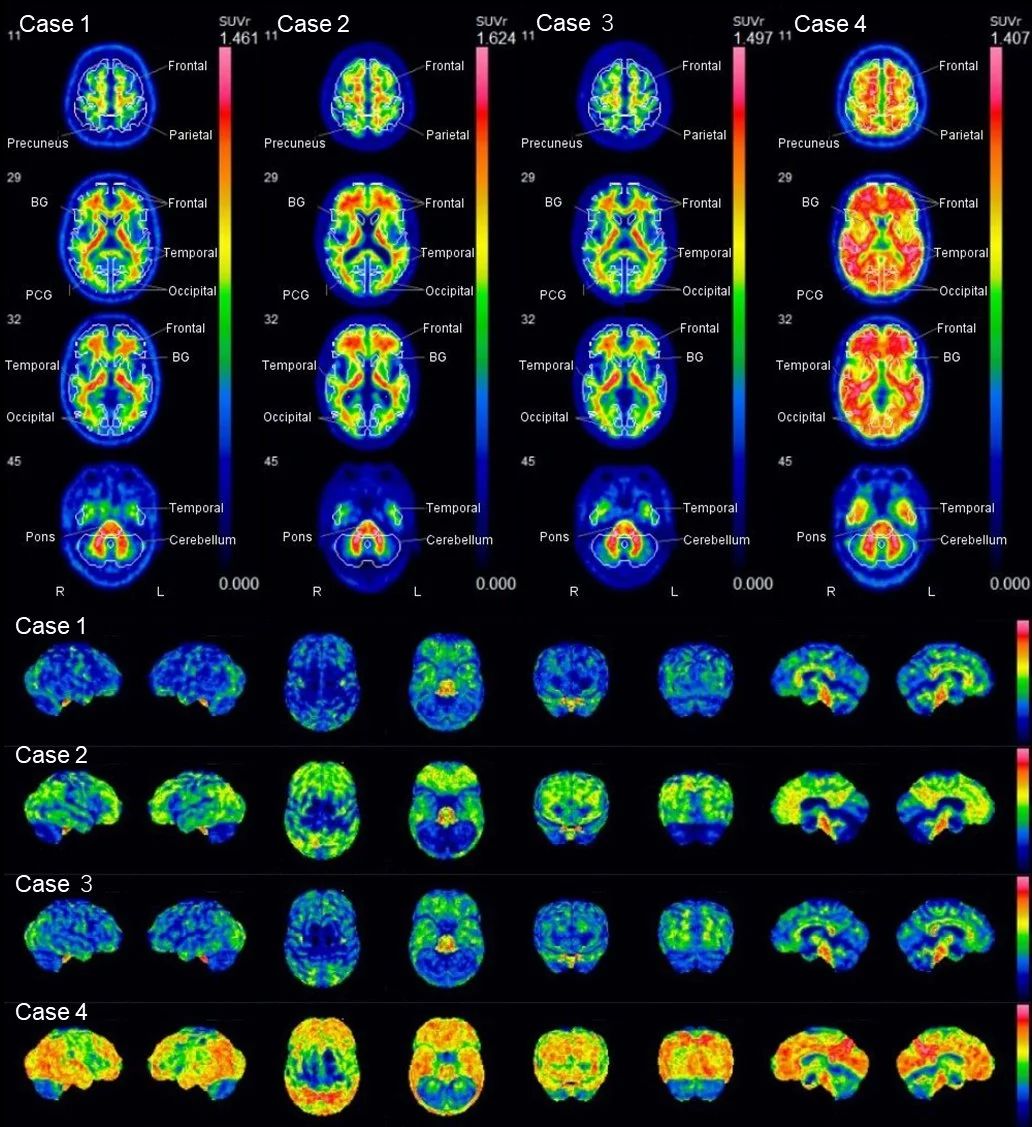

367afe689d7232f4c74c36216edca1b4.jpg

显示了VIZCalc的轴位图像(上排)和带有体素感兴趣区域(VOIs)的表面渲染图像(下排)。病例1和3的淀粉样蛋白为阴性。病例2和4的淀粉样蛋白为阳性。

病例1,56岁男性。复合VOI的标准化摄取值比(SUVr),0.476;Centiloid量表,-11.7。

病例2,79岁男性。复合VOI的标准化摄取值比(SUVr),0.711;Centiloid量表,82.5。

病例3,56岁男性。复合VOI的标准化摄取值比(SUVr),0.517;Centiloid量表,-0.6。

病例4,49岁女性。复合VOI的标准化摄取值比(SUVr),0.905;Centiloid量表,76.4。